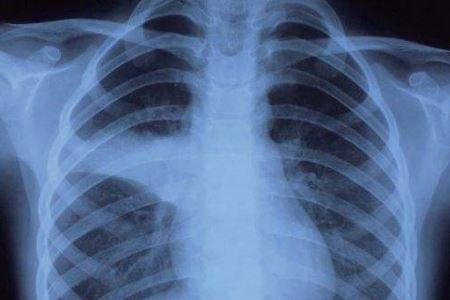

目前国内的疫情不会像前段时间那样严重了,不少地区已经连续一周甚至是十几天都没有新增的病例了。这是个可喜可贺的消息,但是小编提醒,国人们不能大意。因为疫情还未彻底结束,大家仍然要做好自我防护。同时,关注疫情的消息——国内截至3月4日24时新型冠状病毒肺炎疫情最新情况,请认真往下看看。

根据国家卫生健康委员会官方网站公布的数据得知:3月4日0—24时,31个省(自治区、直辖市)和新疆生产建设兵团报告新增确诊病例139例,新增死亡病例31例(湖北31例),新增疑似病例143例。当日新增治愈出院病例2189例,解除医学观察的密切接触者6584人,重症病例减少464例。

截至3月4日24时,据31个省(自治区、直辖市)和新疆生产建设兵团报告,现有确诊病例25352例(其中重症病例5952例),累计治愈出院病例52045例,累计死亡病例3012例,累计报告确诊病例80409例,现有疑似病例522例。累计追踪到密切接触者669025人,尚在医学观察的密切接触者32870人。

湖北新增确诊病例134例(武汉131例),新增治愈出院病例1923例(武汉1426例),新增死亡病例31例(武汉23例),现有确诊病例24085例(武汉21050例),其中重症病例5788例(武汉5342例)。累计治愈出院病例40479例(武汉26316例),累计死亡病例2902例(武汉2305例),累计确诊病例67466例(武汉49671例)。新增疑似病例67例(武汉61例),现有疑似病例315例(武汉247例)。

3月4日0—24时,新增报告境外输入确诊病例2例(浙江2例)。截至3月4日24时,累计报告境外输入确诊病例20例。累计收到港澳台地区通报确诊病例156例:香港特别行政区104例(出院43例,死亡2例),澳门特别行政区10例(出院9例),台湾地区42例(出院12例,死亡1例)。(注:“信息来自国家卫生健康委员会官方网站”。)